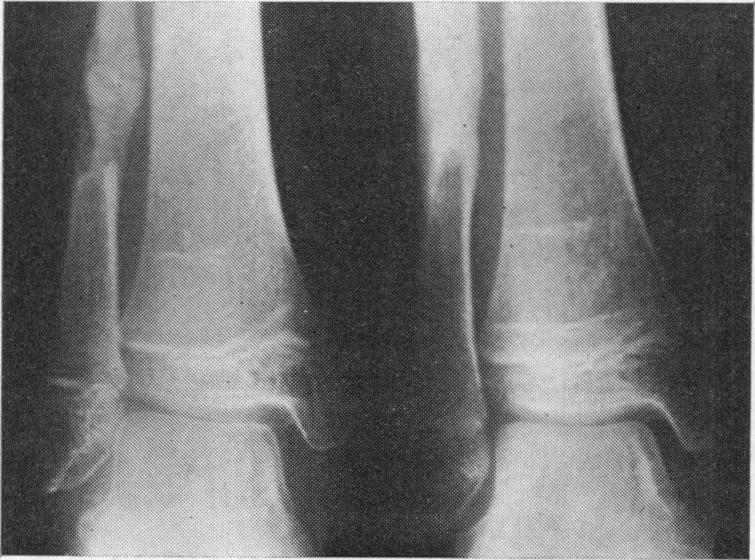

An x-ray study of valgus ankles in spina bifida children with valgus flat foot deformity.

Radiological examination of the ankles of spina bifida children with flail lower limbs and valgus flat foot deformity has revealed a high incidence of abnormal valgus tilt of the ankle-joint. A study of ankle X-rays of spina bifida children before and after extra-articular subtalar fusion in which the bone graft is removed from the ipsilateral tibia has shown that the valgus tilt of the mortice may increase after this procedure.